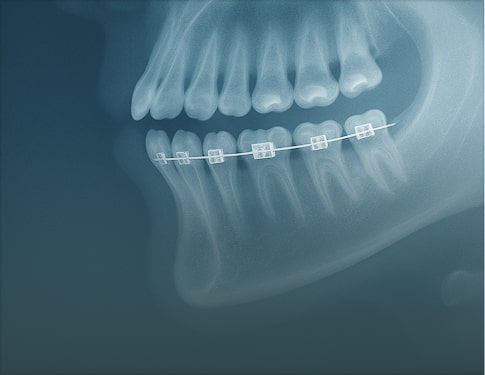

Advanced Report includes annotated images, detailed key findings, and practical clinical recommendations. Choose this option for treatment planning, complex cases, referrals, or when visuals are needed to communicate findings with colleagues or patients and support confident clinical decisions in the final report.